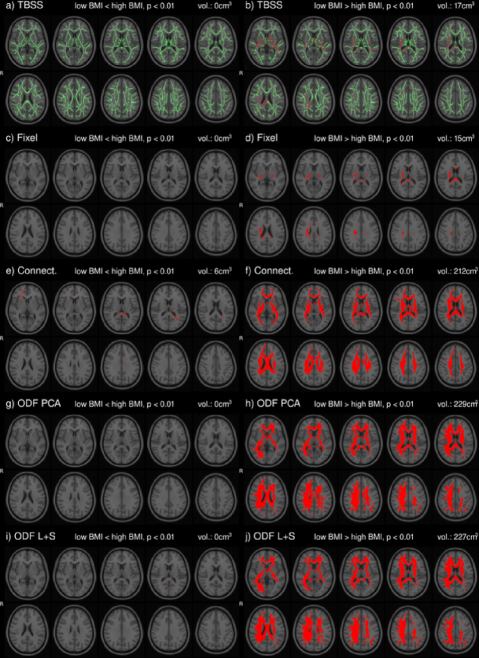

We demonstrate the performance of this ODF approach by replicating the established negative association between global white matter integrity and physical obesity in the Human Connectome dataset. The volume of positive findings (, 227cm3) agrees with and expands on the volume found by TBSS (17cm3), Connectivity based fixel enhancement (15cm3) and Connectometry (212cm3). In the same dataset we further localize the correlations of brain structure with neurocognitive measures such as fluid intelligence and episodic memory.

In the HCP dataset, ODFs correlate strongly with the demographic variable BMI. As expected, the ODFs negatively correlate (Fig. 7b) with BMI, indicating a loss of anisotropy with increasing BMI (Fig. 5a,b). This result is consistent with the well-established negative association between global white matter integrity and physical obesity (Mueller et al., 2011; Stanek et al., 2011; Verstynen et al., 2012; Gianaros et al., 2013; Verstynen et al., 2013). The fiber directions (Fig. 8a,b) identified from can be used to perform tractography (Fig. 8c,d). Resulting tracts (Fig. 8c,d) show a pronounced loss of anisotropy in the corticospinal tracts, the optic radiations and the right superior longitudinal fasciculus. These results are corroborated by the existing methods TBSS (Fig. 9a,b, S2a,b), Connectivity-based fixel enhancement (Fig. 9c,d, S2c,d) and local connectometry (Fig. 9e,f, S3a,b). The volume of positive findings of correlation with BMI is largest when using the full ODF information with the ODF approach (Fig. 9). In addition, in a test of specificity, no voxels are found to correlate with randomly permuted BMI (Fig. S4).

The individual variability of ODFs can be caused by ODF reconstruction errors due to image artifacts (Fig. S5.1), registration errors and individual differences in brain structure (Fig. S5.3-4). In the HCP ODFs individual variability due to the first two of these contributions is limited by the low number of artifacts and the high image resolution in the HCP DWI images. As a result, ODF correlations of BMI identified with ODF ((Fig. 9g,h, S3c,d)) and ODF (Fig. 9i,j, 7) are similar in this dataset. However, in a dataset with higher individual variation, notable improvement of ODF over ODF PCA can be observed (Baete et al., 2016a).

Several methods exist to analyze populations of diffusion MRI datasets, typically working on a reduced dimensionality subset of the diffusion data. TBSS (Jbabdi et al., 2010), limiting the analysis to a projection to a tract skeleton, succeeds in identifying the tracts most significantly correlated with BMI (analysis of FA, Fig. 9a,b, S2a,b) but misses the full extent of the correlations. The Connectivity-based fixel enhancement (Raffelt et al., 2015) and Connectometry (Yeh et al., 2016) approaches do include more of the available information and hence perform better than the TBSS method (Fig. 9c,d, S2c,d (Fixel enhancement) and 9e,f, S3a,b (Connectometry) vs 9a,b, S2a,b (TBSS)).

None of the above methods however capitalizes on the full ODF information. This in contrast to the approach presented in this paper. The ODF approach indeed identifies a larger volume of significant findings (227 cm3) than the existing methods tested here (TBSS 17 cm3, Connectivity-based fixel enhancement 15 cm3 and Connectometry 212 cm3, Fig. 9b,d,f,h,j). That is, by analyzing the full ODF information and not reducing the dimensionality of the diffusion data, as is commonly done, the ODF approach is able to pick up on smaller significant changes, better grasping the full extent of the significant findings. Limitations on computational power and diffusion acquisitions (e.g. DTI) which inspired the data reduction of older methods no longer exist. It is hence advisable to maximize the amount of information included in the analysis as in the approach presented here.